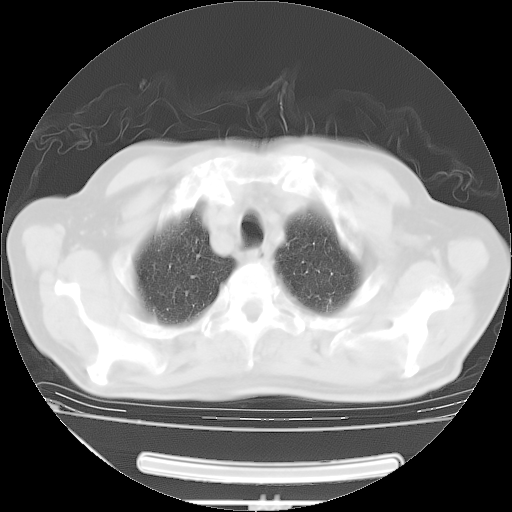

今天复查肺部CT,发现双肺广泛磨玻璃样改变。所以我把3月19日和5月9日相隔50天的肺部CT上传。请大家会诊。

2009年3月19日肺部CT片。

2009年3月19日肺部CT

大致读了系列胸部CT:纵隔窗无明显异常,肺窗:从4、27至今:主要是双肺中下野外带可见毛玻璃样改变,目前处于急性肺泡炎阶段,至于原因考虑1、结替组织或胶原血管性疾病所致?2、恶性疾病如恶组在肺部所致的表现或细支气管肺泡癌?3、药物或其它原因如肺蛋白沉着症所致肺泡炎目前不太可能?总之,明天就去请我院的呼吸科、感染科、血液科和临免专家会诊哈。